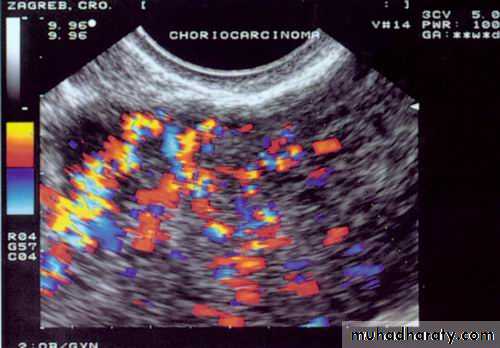

absence of chorionic villiDoppler image of choriocarcinoma

Doppler image of choriocarcinoma

Ultrasound and doppler examination